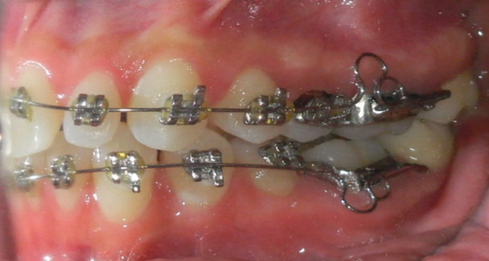

Denise llego con un tratamiento de ortodoncia con mas de 3 años y no estaba contenta con los resultados. Se le quitaron los braquets y pusimos nuestra técnica, 7 meses después se le tomaron fotografías de control.

Con muy buen resultado como se observa en las fotos, de lado izquierdo es como llego y de lado derecho como está actualmente.